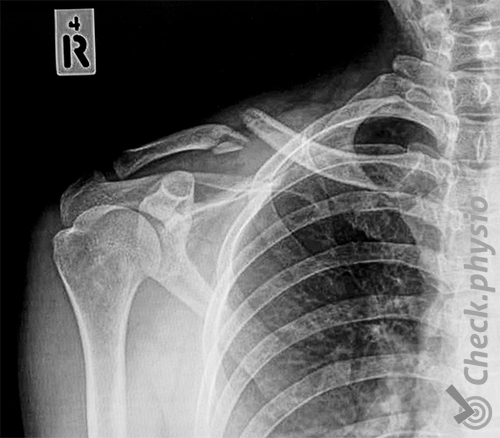

Et brudd i kragebeinet er lett å diagnostisere fordi kragebeinet ligger så overfladisk. Bruddet kan derfor ofte ses og føles tydelig. Et røntgen tas vanligvis for å få innsikt i bruddet og vinklingen av beinet. Dette gir informasjon om helingsprosessen og kan avkrefte skade på underliggende vev som nerver og blodårer.

Dersom røntgenbildene viser betydelig forskyvning i bruddet eller at det er et ustabilt brudd, vurderes operasjon.